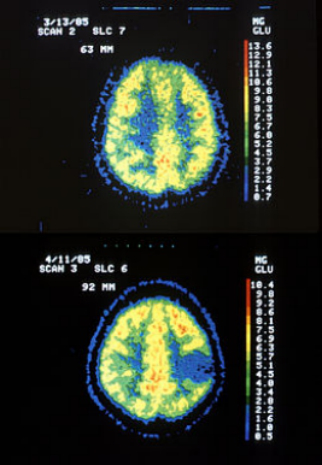

而胶质瘤质子治疗,就是指氢原子剥去电子后带有正电荷的粒子。氢原子通过回旋加速器或同步加速器高能加速,成为穿透力很强的电离放射线,这就是质子射线。在质子线治疗中,可利用专门的机器和器具,结合布拉格峰的深度和患者不同病灶的形状进行照射。因此可集中剂量,只瞄准病灶实施照射,对周边正常组织的影响微乎其微。由于大脑是人体的总司令部,过高的放射剂量会伤害正常脑组织,而造成一些不可逆的神经损伤,通过图像定位的准确质子放疗可以在保护周边正常脑组织的前提下,对肿瘤病灶起到很好的杀伤作用。